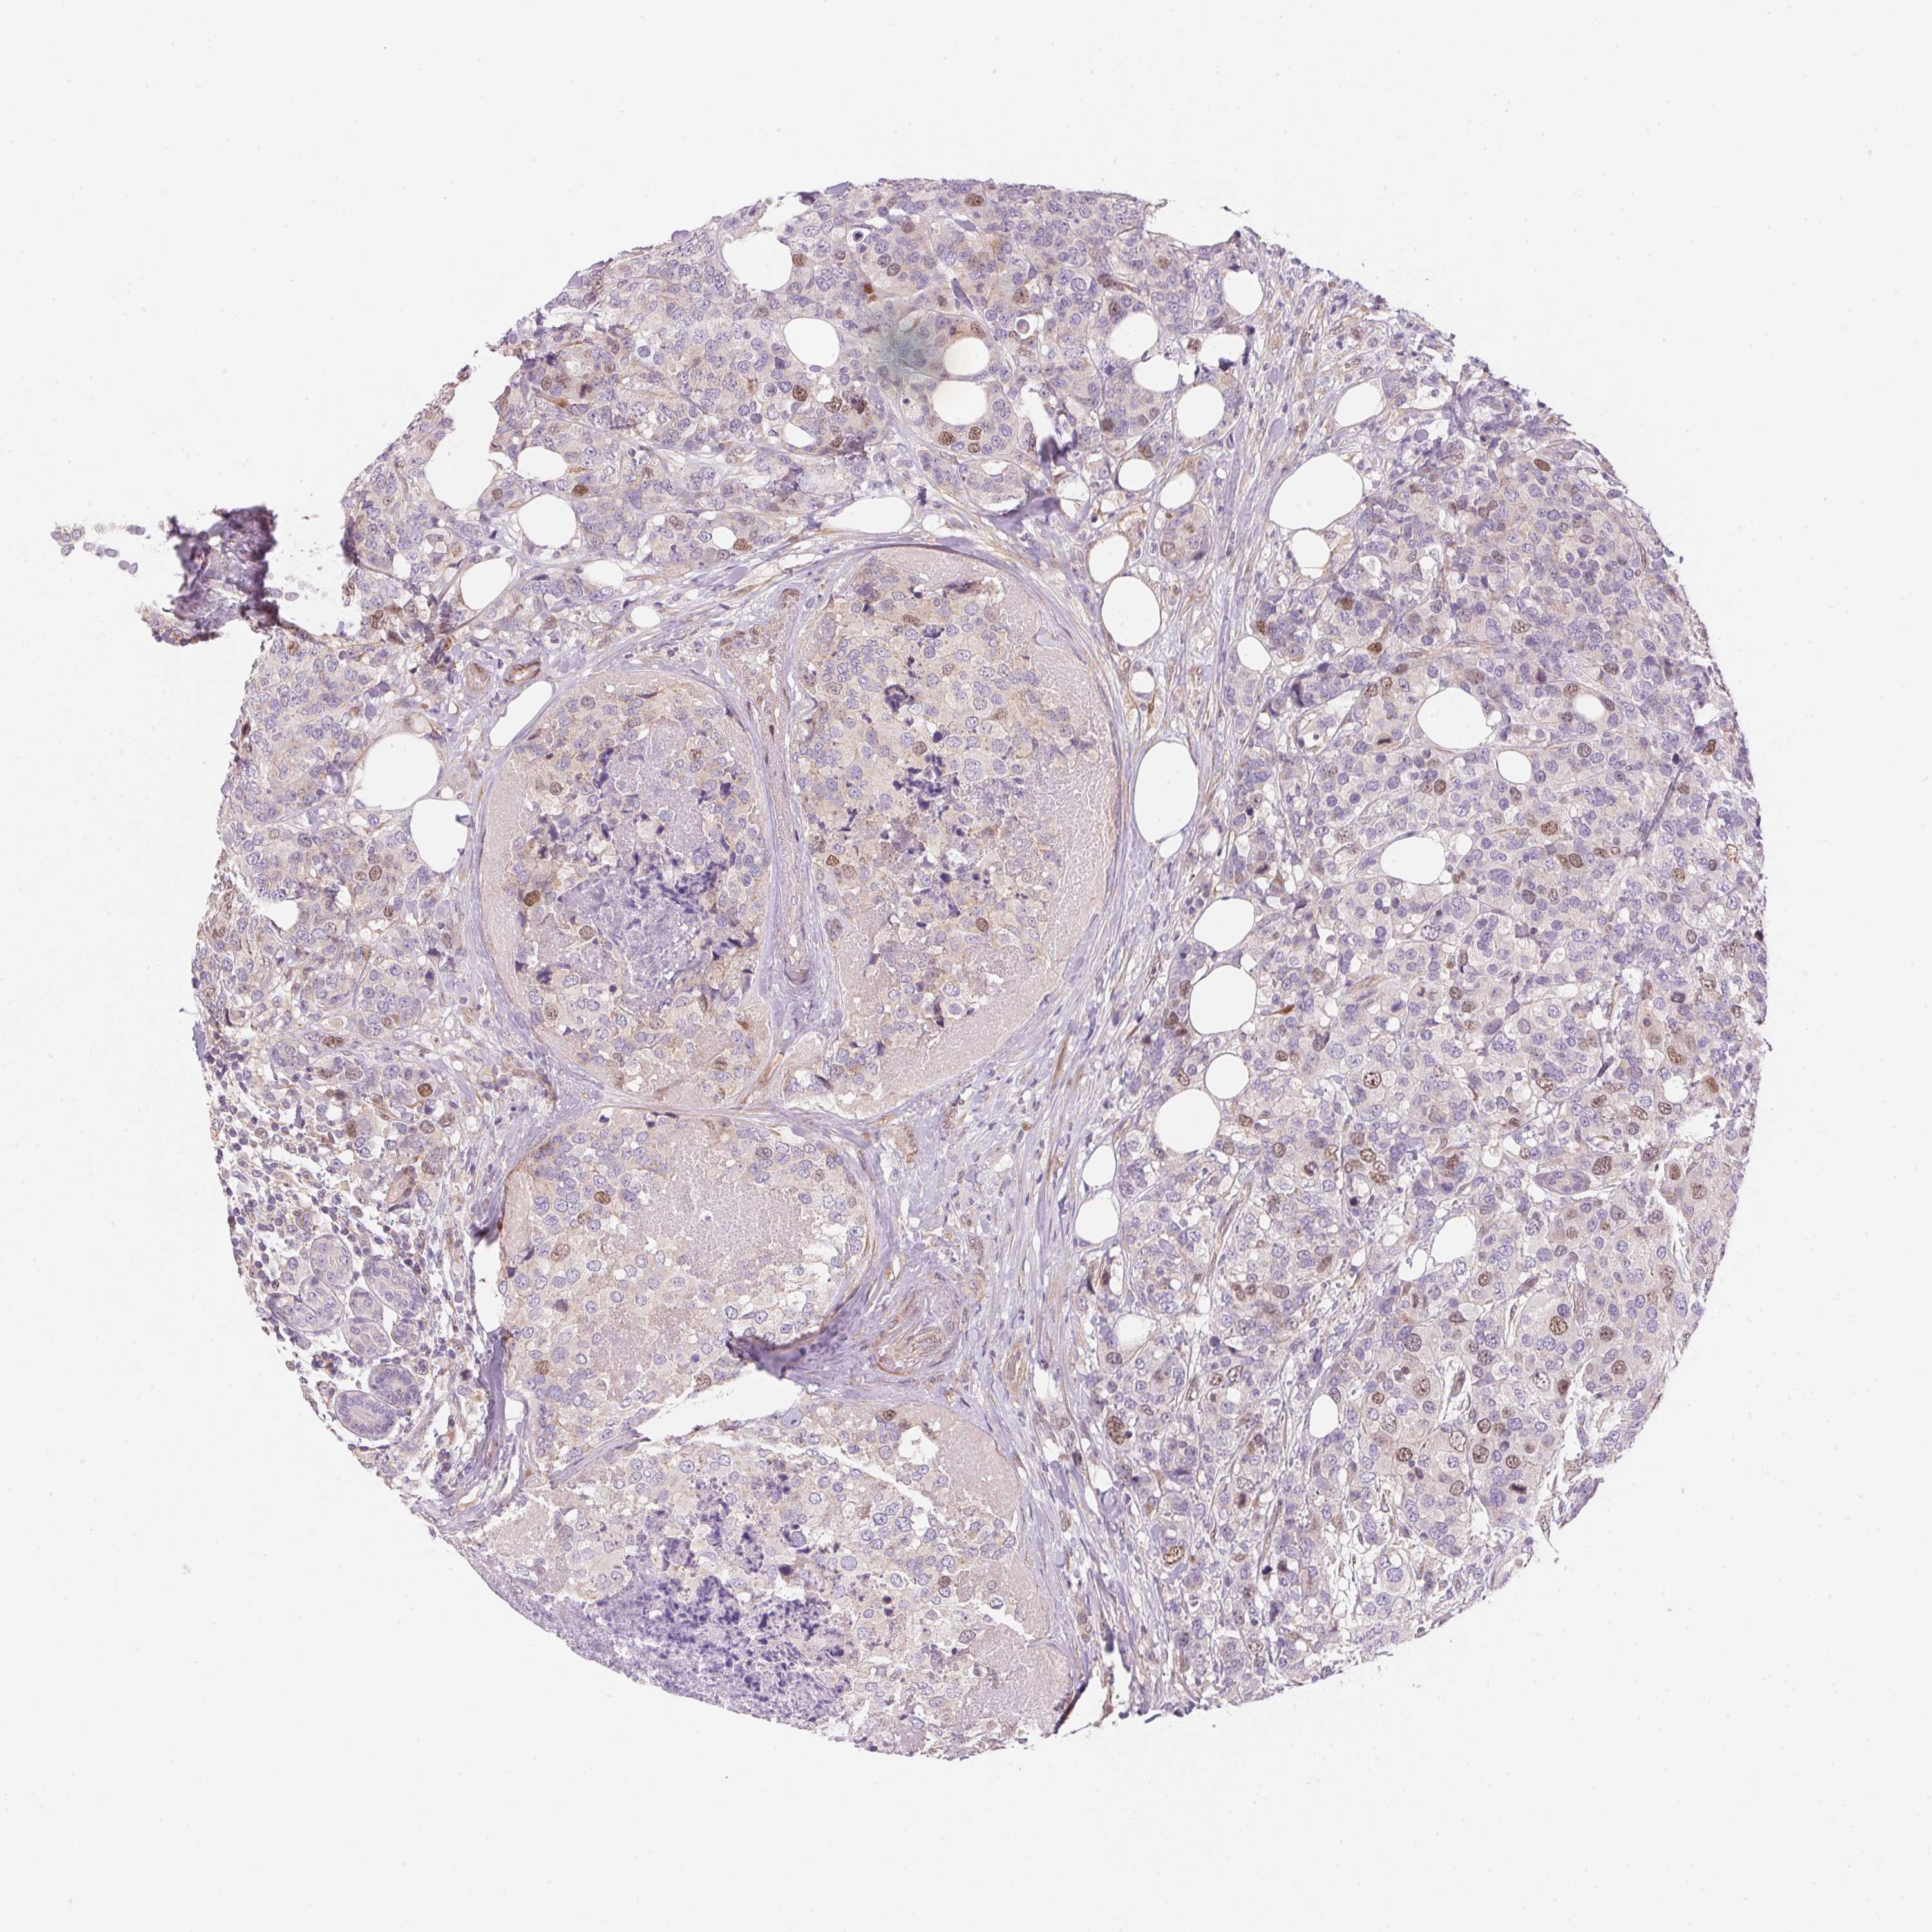

CANCER BREAST CANCER Show tissue menu

BRCA TCGA BRCA VALIDATION PROTEIN EXPRESSION